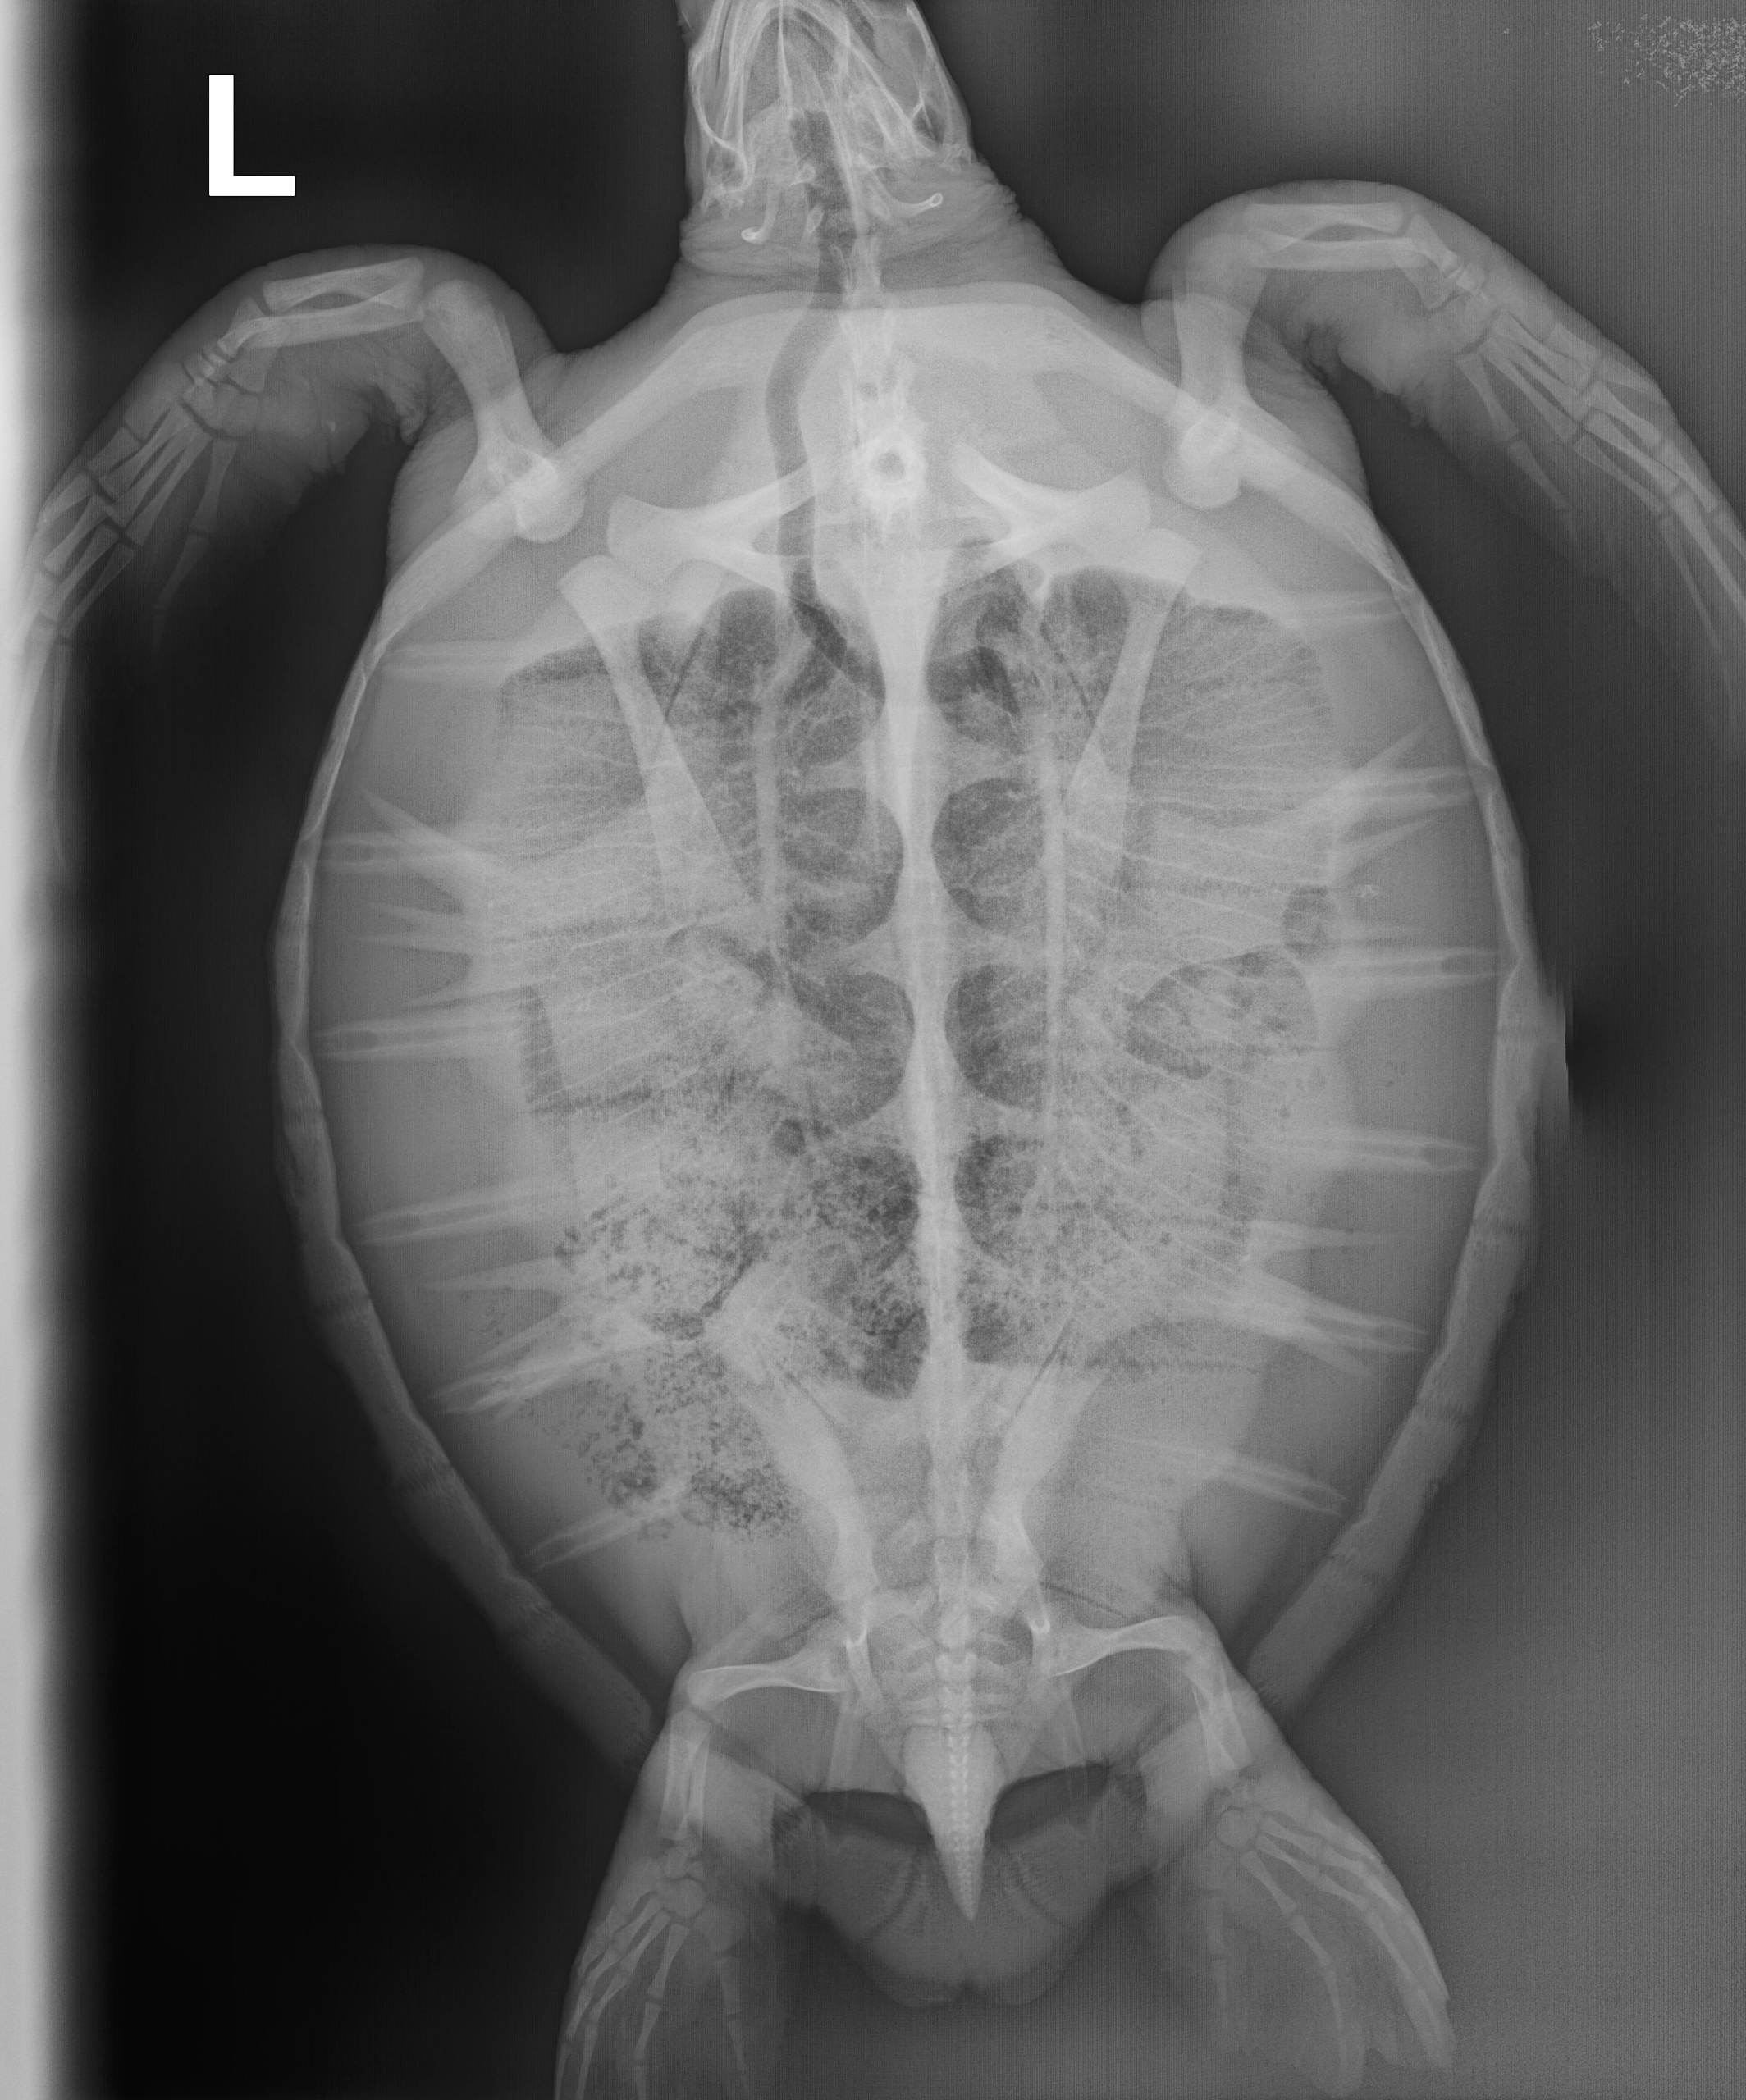

9.1 lbs. non-FP juvenile green

Hook in left front flipper and moderate abrasions on plastron and on all flippers.

In-house PCV = 36%, TP = 3.8 g/dl, glucose = 89. Started on Ceftaz, Vitamin B, and Normosol.